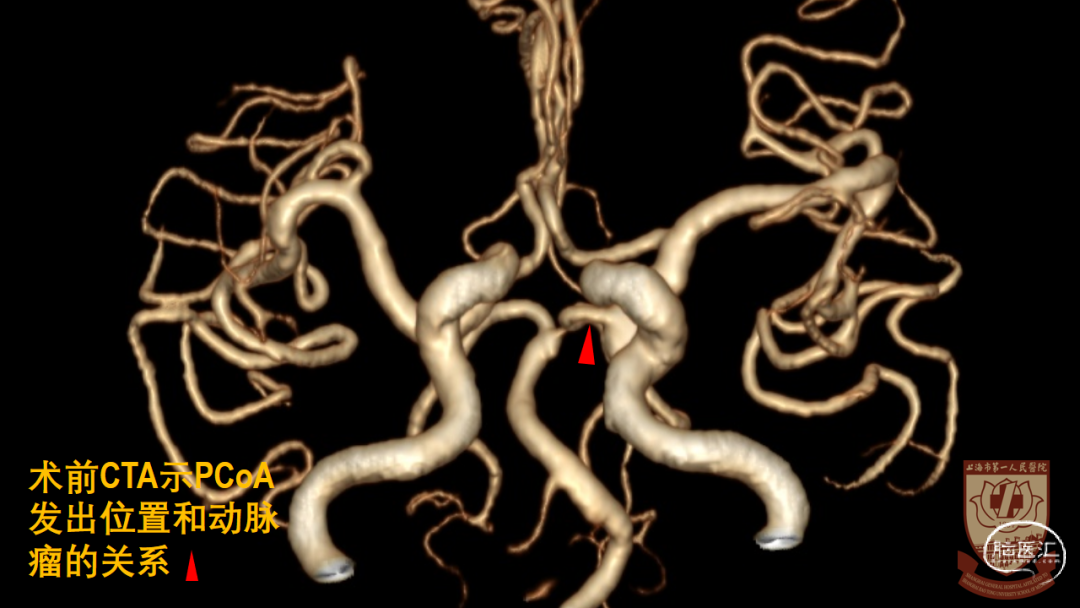

CTA:左侧大型后交通动脉瘤,指向后、外、下